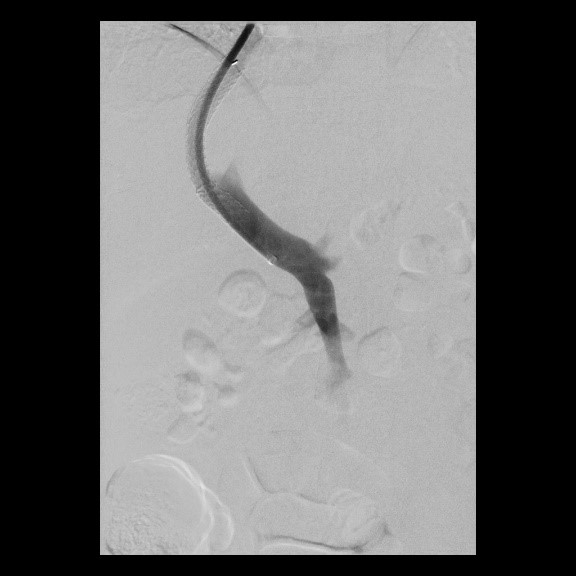

Aortenkoarktationsstenose vor Stentimplantation

(Bild 1 von 4)